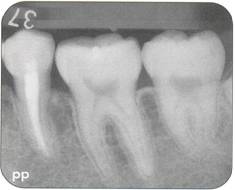

Fi 545e45f g 5-1d Preoperative periapical radiograph. |

Fi 545e45f g 5-8i Radiographic evaluation of the donor tooth. Several angulations should be used to determine the likely fit of the donor tooth into the recipient site. If the first premolar is double-rooted, consider using the second premolar as a donor tooth. |